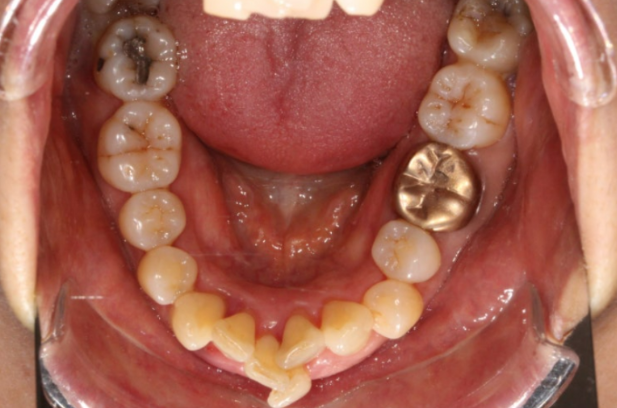

2022.11

돌출과 삐뚠 치아 때문에 오래전 상담했을 때에는 작은 어금니 4개를 발치해야 한다고 설명을 들으셨다고 합니다.

아래 앞니 2개를 빼면 위에도 2개를 빼야한다고 생각하기 쉽지만 정밀 진단을 통해 위에는 발치 없이 사랑니 공간을 이용하여 뒤로 미는 치료를 하기로 했습니다.

그 이유는 환자분의 인중 길이에 있습니다.

치료 전 안모에서 앞니 돌출에 의한 입술 부전증과 함께 하관에 비해 인중이 긴 편임으로 알 수 있습니다.

위에까지 발치를 하면 입이 너무 많이 들어갈 가능성이 있습니다.

교정 후 인중까지 더 길어보이는 부작용이 생길 수 있습니다.

그래서 최종 치료계획은 위에 발치 없이 사랑니 공간을 이용해서 돌출을 해소하고 아래는 살릴 수 없는 앞니 2개를 발치 후 송곳니를 앞니 자리로 끌어와서 앞니처럼 쓰기로 했습니다.